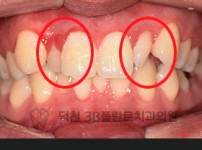

치료전후